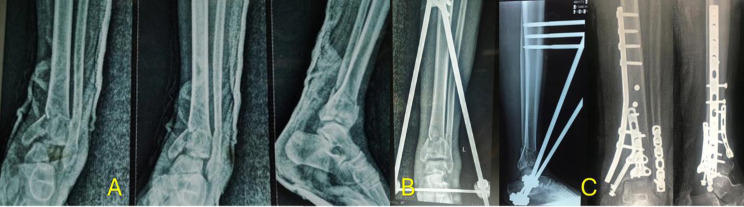

Objectives: Pilon fractures are among the difficult injuries to treat in orthopedic surgery. We aim to evaluate the feasibility, advantages, and disadvantages of temporary external fixation for pilon fractures and compare its outcomes with cases managed with internal fixation and primary open reduction.

Methods: In a prospective trial, 30 patients were divided into two cohorts: a two-stage cohort with external fixation and secondary ORIF (15 patients) and a one-stage primary ORIF cohort (15 patients). We compared the two cohorts' rates of infection (deep or superficial infection), non-union, malunion, length of hospital stay, patient satisfaction with the American Orthopaedic Foot and Ankle Society (AOFAS) score, and pain level.

Abstract Image